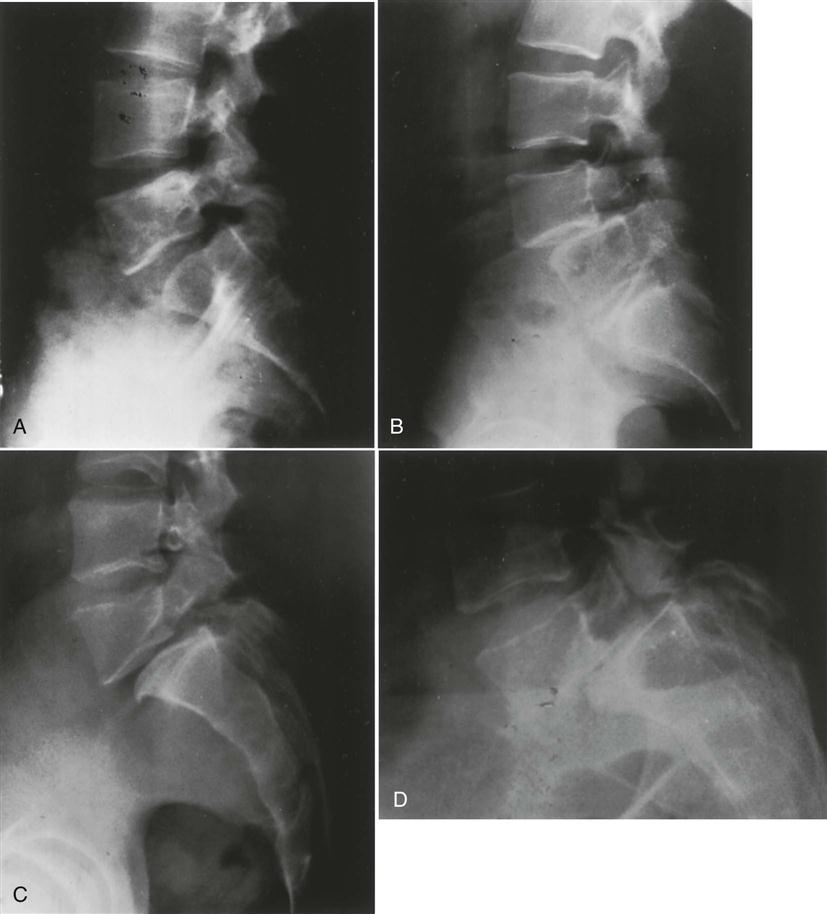

Normally, anteroposterior and lateral views are taken.258 In some cases, two lateral views may be taken, one that shows the whole lumbar spine, and one that focuses on the lower two segments. Oblique views are taken if spondylolysis or spondylolisthesis is suspected.123

With this view (Figure 9-106), the examiner should note the following:

1. Any evidence of spondylosis or spondylolisthesis, which occurs in 2% to 4% of the population (Figure 9-107). The degree of slipping can be graded as shown in Figure 9-108.259 New grading or classification system involving lateral sacropelvic and spinopelvic balance have also been suggested.260

2. A normal lordosis. Do the intervertebral foramina appear normal?

3. Any wedging of the vertebrae.

5. Alignment of the vertebrae should be noted. Disruption of the curve may indicate spinal instability.

6. Any osteophyte formation or traction spurs (Figure 9-109).251,261 Traction spurs indicate an unstable lumbar intervertebral segment. A traction spur occurs approximately 1 mm from the disc border; an osteophyte occurs at the disc border with the vertebral body.

With the oblique view (Figure 9-110), the examiner should look for any evidence of spondylolisthesis (sometimes referred to as a “Scottie dog decapitated”) or spondylolysis (sometimes referred to as a “Scottie dog with a collar;” Figure 9-111).

In some cases, motion views may be used to demonstrate abnormal spinal motion or structural abnormalities. These are usually lateral views showing flexion and extension to demonstrate instability or spondylolisthesis (Figure 9-112), but they may also include anteroposterior views with side bending.166,262,263